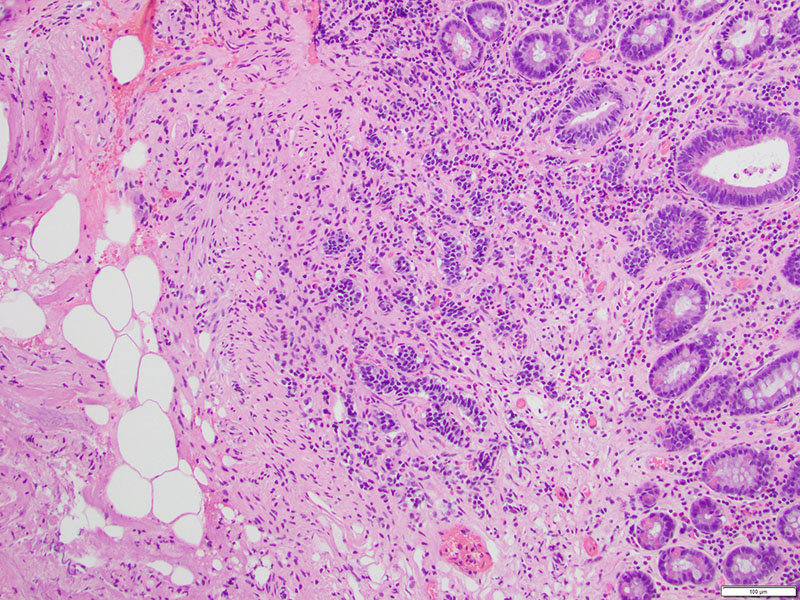

The patient is sent for an esophagogastroduodenoscopy (EGD), which reveals a 2 c.m. polyp in the third segment of the duodenum. Biopsy confirms duodenal adenoma, for which the patient elects to undergo an EGD with endoscopic mucosal resection (EMR).Microscopic examination demonstrates duodenal mucosa with low-grade epithelial dysplasia overlying foci of bland, monotonous cells with scant cytoplasm (Figures 1 & 2). The cells are arranged in nests and trabeculae that infiltrate into the superficial muscularis mucosae (Figure 3). Immunohistochemistry shows positive staining for synaptophysin (Figure 4) and chromogranin (Figure 5), as well as a Ki-67 labeling index < 1% (Figure 6).